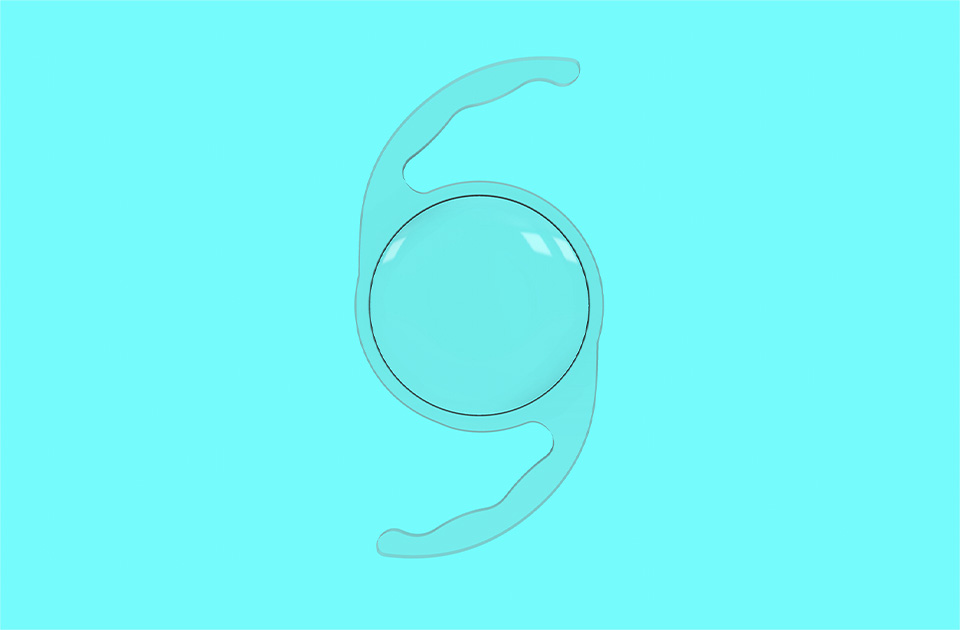

眼内レンズには「単焦点レンズ」と「多焦点レンズ」の2タイプがあります。

単焦点レンズは、特定の距離にだけピントを合わせる仕組みとなっているため、予定した特定の距離ではクリアな視界が得られますが、ほかの距離を見る際には眼鏡が必要です。一方、多焦点レンズは、遠距離・中距離・近距離のうち2つの距離にピントを合わせることが可能となります。眼鏡の頻度が減り、より幅広い距離で視界が得られます。

主に「遠くと近くが見える遠近両用レンズ」と「遠くから中間距離まで幅広く見えるレンズ」の2種類のレンズがあります。ライフスタイルに応じてレンズを選択することで、眼鏡の使用頻度を減らし、より快適な生活を送れる可能性が高まります。